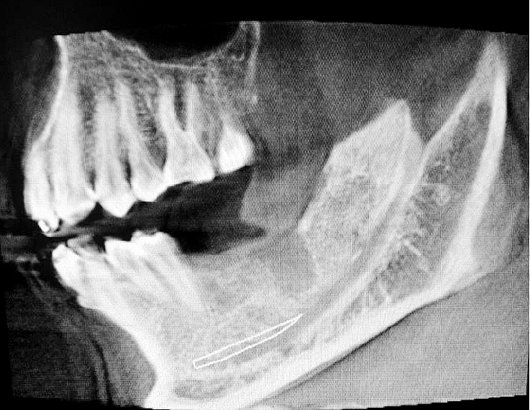

2016.8.3涉縣美康口腔王主任種植牙于額外牙拔除

左下67缺失

ct定位